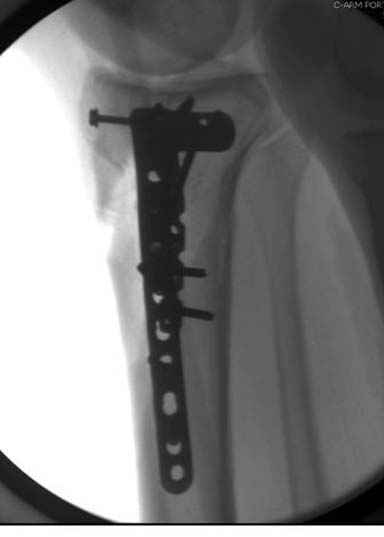

Решили выполнить остеосинтез штифтом и внутрисуставного перелома пластиной и винтами. Жду мнения! Зачем мне оправдываться-я же не преступник. Диалогом называется...

При переломах одного из мыщелков тибиал плато+дополнительный перелом проксимальной трети большеберцовой кости можно применить комбинированный вариант фиксации, т.е. мыщелок винтами или пластиной, а для диафиза можно установить гвоздь. В данном варианте потеряно преимущество гвоздя , из-за серьезной травмы суставной поверхности нельзя нагружать ногу несколько месяцев. А без нагрузки гвоздь просто заполнитель пространства внутри кости!

На вашем место я бы подождал с фиксацией до готовности кожных покровов, и за это время можно было подобрать соответствующий фиксатор, т.е более длинная пластина снаружи и медиальная пластина на апексе перелома как подпорка. Здесь приемлем как раз минимальный доступ.

Здесь пару случаев для сравнения,...в первых 1-4 слайдах метод фиксации одним фиксатором, как видно после 8 месяцев сохранилась ось. С 5 по 9 вариант двумя пластинами...

Согласен с постами докторов Кульджанова и Волны. В данном случае мы не отмечаем признаков тщательного предоперационного планирования, что сказалось на характере принятого решения и его результате. В нашей клинике, мы бы использовали длинную блокированную пластину по латеральной поверхности, через проксимальное окно отрепонировали бы суставную поверхность, через дистальное фиксация 3-4 винтами в с/3 б/берцовой кости. По медиальной поверхности в качестве поддержки - 1/3 трубчастая или реконструктивная пластина. С большой долей вероятности использовали бы костную аутопластику.